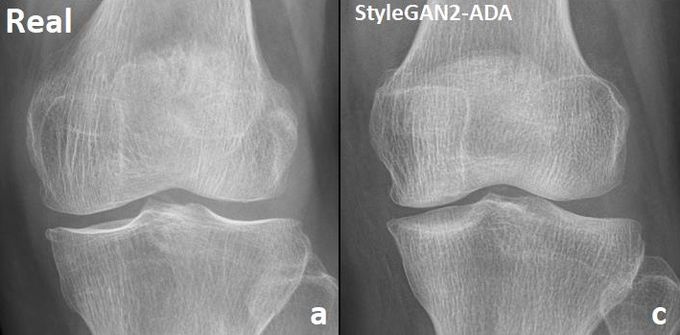

[µ¥Àϸ®¸Þµð ¹Ú´ëÁø ±âÀÚ] Àü¹®°¡µµ ±¸ºÐÇÒ ¼ö ¾øÀ» Á¤µµÀÇ ¹«¸­ °üÀý¿° ÇÕ¼º X-ray µ¥ÀÌÅͰ¡ °³¹ßµÆ´Ù.

¼­¿ï´ëº´¿ø Á¤Çü¿Ü°ú ³ëµÎÇö ±³¼öÆÀÀº ÀΰøÁö´ÉÀÎ »ý¼ºÀû Àû´ë ½Å°æ¸ÁÀ» ÀÌ¿ëÇØ °íÇØ»óµµ·°íǰÁú ¹«¸­ °üÀý¿° X-ray À̹ÌÁö¸¦ »ý¼ºÇÏ´Â ¸ðµ¨À» °³¹ßÇß´Ù°í 31ÀÏ ¹àÇû´Ù.

»ý¼ºÀû Àû´ë ½Å°æ¸Á(Generative Adversarial Network, GAN)Àº ´ëÇ¥ÀûÀÎ ÇÕ¼º µ¥ÀÌÅÍ ±â¼ú·Î »ç¶÷ÀÇ ´«¿¡ ¸Å¿ì »ç½ÇÀûÀ̰í Çö½ÇÀûÀÎ À̹ÌÁö¸¦ »ý¼ºÇÑ´Ù.

°¡Â¥ µ¥ÀÌÅ͸¦ »ý¼ºÇÏ´Â »ý¼º±â¿Í ÁøÂ¥¿Í °¡Â¥¸¦ ±¸ºÐÇÏ´Â ÆÇº°±â°¡ °æÀïÀûÀ¸·Î ÇнÀÇØ ÁøÂ¥ µ¥ÀÌÅÍ¿¡ °¡±î¿î °¡Â¥ µ¥ÀÌÅ͸¦ »ý¼ºÇÑ´Ù.

¿¬±¸ÆÀÀº ¼­¿ï´ëº´¿ø¿¡ ³»¿øÇÑ È¯ÀÚ 1¸¸¸íÀÇ ¹«¸­ X-ray À̹ÌÁö¸¦ Á¤Á¦ ¹× ºÐ¼®Çß°í »ý¼ºÀû Àû´ë ½Å°æ¸Á(GAN)À» °³¹ßÇß´Ù. ±× ÈÄ »ý¼ºµÈ À̹ÌÁöÀÇ ½Å·Úµµ ¼öÄ¡¸¦ Æò°¡Çß´Ù.

À̹ø ¿¬±¸¿¡¼­´Â ½Å·ÚÇÒ ¼ö ÀÖ´Â µ¥ÀÌÅ͸¦ ¸¸µé±â À§ÇØ ÃÖ¼Ò 2000Àå ÀÌ»óÀÇ ¿µ»óÀÌ ÇÊ¿äÇÔÀ» È®ÀÎÇß´Ù. »ý¼ºµÈ À̹ÌÁö´Â ÄÄÇ»ÅÍ ¾Ë°í¸®ÁòÀ¸·Îµµ ¿øº»°ú ±¸ºÐÀÌ Èûµé¾ú´Ù.

ÀÌÈÄ Á¤Çü¿Ü°ú Àü¹®ÀÇ 2¸í, ÄÄÇ»ÅÍ ºñÀü Àü¹®°¡ 2¸í, ¿µ»óÀÇÇаú Àü¹®ÀÇ 1¸í µî ´Ù¾çÇÑ Àü¹®°¡µéÀÌ »ý¼ºµÈ À̹ÌÁöÀÇ Ç°ÁúÀ» ºÐ¼®Çß´Ù.

¿ì¼± À̹ÌÁöÀÇ ¼º´ÉÀ» °ËÁõÇϱâ À§ÇØ ÁøÂ¥ À̹ÌÁö¿Í »ý¼ºµÈ À̹ÌÁö¸¦ ±¸º°ÇÏ´Â Æ©¸µÅ×½ºÆ®(Turing test)¸¦ ÁøÇàÇß´Ù.

°¢°¢ 50°³ÀÇ ½ÇÁ¦ ¹× »ý¼ºµÈ À̹ÌÁö°¡ È¥ÇÕµÈ 100°³ÀÇ À̹ÌÁö¸¦ ºÐ·ùÇÏ´Â Å×½ºÆ®¿¡¼­ Àü¹®°¡ 5¸íÀÇ ºÐ·ù Á¤È®µµ´Â 34%, 44%, 46%, 57%, 50%·Î ³ª¿Ô´Ù.

Å×½ºÆ® °á°ú´Â Àü¹®Àǵµ ½ÇÁ¦¿Í »ý¼º¹°À» È®½ÇÇÏ°Ô ±¸º°Çϱâ Èûµé´Ù´Â °ÍÀ» º¸¿©ÁØ´Ù.

¶ÇÇÑ ¿¬±¸ÆÀÀº »ý¼ºµÈ À̹ÌÁöÀÇ ÁúÀû ºÐ¼®µµ ½Ç½ÃÇß´Ù. Áúº´ °íÀ¯ÀÇ ÇØºÎÇÐÀû Ư¼ºÀ̳ª À±°û¼±, »À Å׵θ®, °üÀý µîÀÇ À̹ÌÁö ǰÁúÀ» ºÐ¼®ÇÑ °á°ú ½ÇÁ¦ À̹ÌÁö¿Í ¸Å¿ì Èí»çÇß´Ù.

¿¬±¸°á°ú´Â ½ÉÃþÇнÀ Áß »ý¼ºÀû Àû´ë ½Å°æ¸ÁÀ» ÀÌ¿ëÇØ Àü¹®°¡µµ ±¸ºÐÇϱâ Èûµç ÇÕ¼º ÀÍ¸í µ¥ÀÌÅ͸¦ ¸¸µé¾ú´Ù´Â Á¡¿¡¼­ ÀÇÀǰ¡ ÀÖ´Ù.